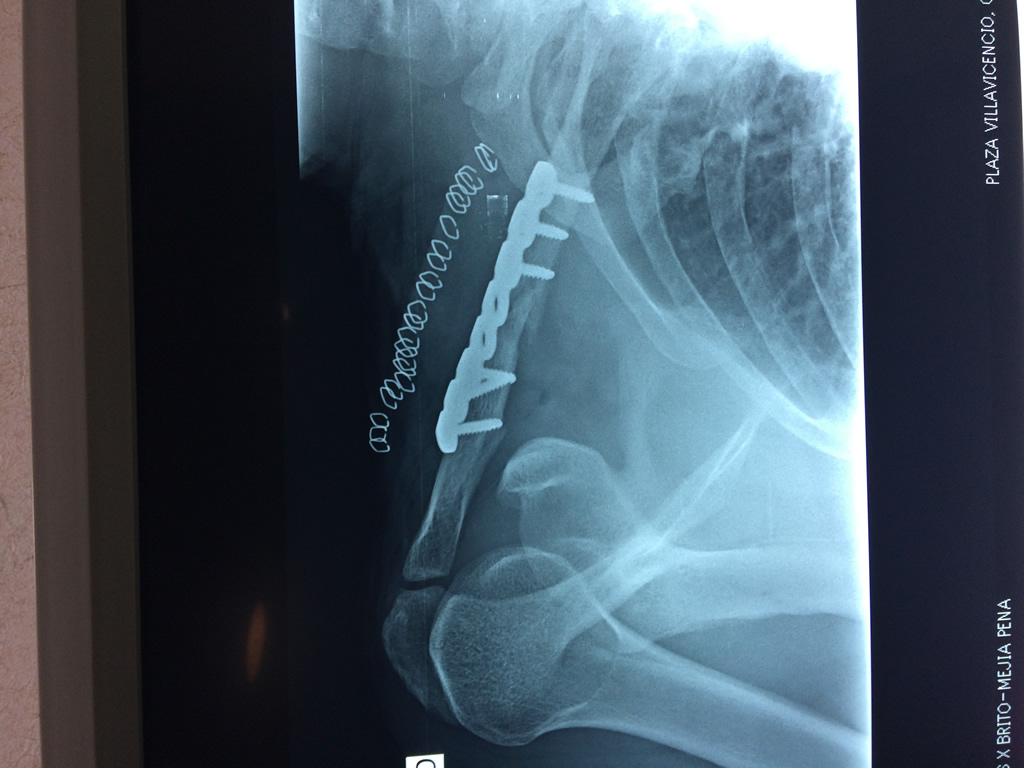

Cirugías